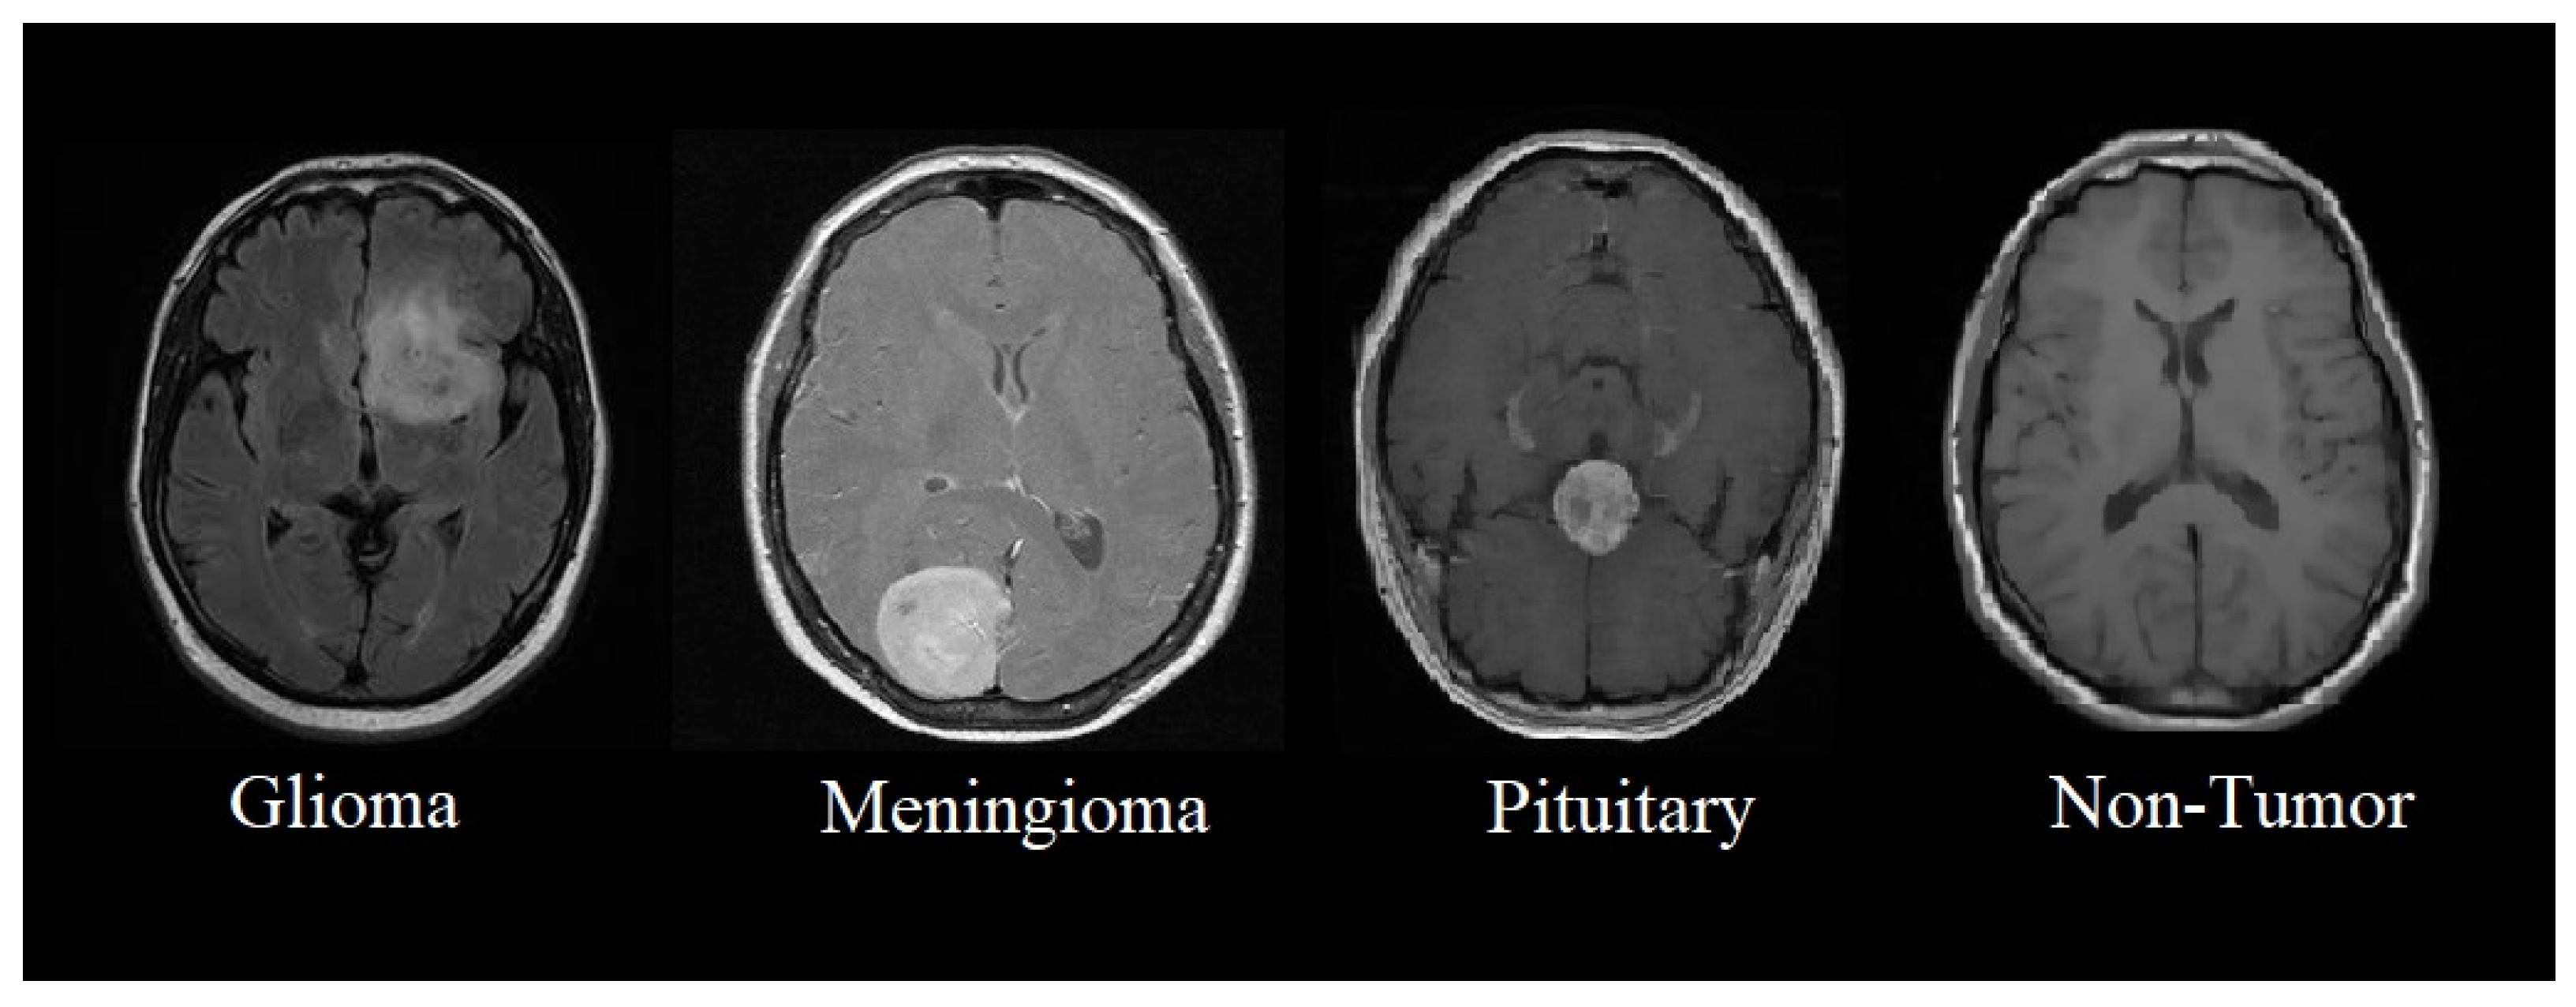

This section presents the proposed methodology of a multi-scale CNN model for identifying and classifying brain tumors in four classes such as glioma, meningioma, pituitary, and non-tumor MRI. The proposed multi-scale model aims to perform multi-class classification, where brain tumors are classified into four classes, as shown in Figure 1.

Figure 1. Classification of brain tumors from MRIs.